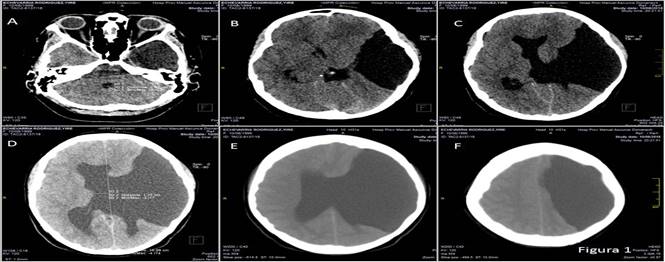

Los estudios hemoquímicos y gasométricos se encontraban dentro de los parámetros normales y se descartó la presencia de una enfermedad infecciosa del sistema nervioso central por lo que se procedió a la realización de la tomografía axial computarizada (TAC), donde se observó la presencia de una imagen hipodensa en comunicación con el ventrículo lateral izquierdo que producía efecto de masa a nivel de la línea media con desviación de 7 mm hacia la derecha con agenesia del cuerpo calloso, escasa diferenciación de la sustancia gris-blanca del lado derecho, tercer ventrículo de aspecto normal. Cisternas basales colapsadas, cuarto ventrículo de 9 mm e hipoplasia del seno frontal izquierdo. Estos hallazgos se interpretaron como una esquizencefalia unilateral de labio abierto por lo que se presumió que el deterioro neurológico se relacionaba directamente con los hallazgos tomográficos (Figura 1).

Se practicó de urgencia, una derivación ventricular izquierda al exterior con el objetivo diagnóstico y terapéutico de aliviar la hipertensión del líquido cefalorraquídeo y monitorizar la presión intracraneal, que se mantuvo en valores entre los 250 y 300 mm de H2O. El estudio evolutivo por TAC evidenció el agujero de trépano frontal izquierdo con catéter de derivación y las estructuras de línea media estaban desplazadas menos de 5 mm. Al examen físico, la paciente recobra su nivel de consciencia y se toma la decisión de colocar un sistema derivativo ventrículo peritoneal. La cirugía no mostró complicaciones y la paciente se restableció. Fue egresada del hospital con completa recuperación neurológica de la consciencia, el defecto motor de iguales características y sin convulsiones sobreañadidas (Figura 2).